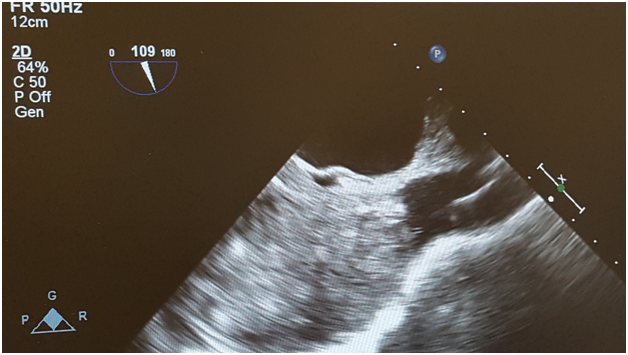

There was great concern regarding safe induction of anesthesia due to a near complete obstruction of superior vena cava (SVC). The patient was volume loaded with 500 milliliters of 5% albumin, 1.5 liters of crystalloid and 2 units of packed red blood cells. A right radial arterial line was placed preinduction. General anesthesia was delivered carefully using a induction regimen consisting of etomidate/ fentanyl/ midazolam and rocuronium for muscle relaxation. Surgeons were present in the operating room for induction. After induction of general anesthesia, a multiplane transesophageal echocardiography probe was inserted into the esophagus without difficulty. Transesophageal echocardiography revealed a very large mass in the severly dilated right atrium; the attachment point was not completely clear, but may have involved the atrial septum. The interatrial septum was intact with no evidence for an atrial septal defect. There was also mild to moderate tricuspid regurgitation. Left ventricle was normal in size with ejection fraction 55% (Figures 1 & 2). The patient remained hemodynamically stable throughout the case.

Figure 1: Transesophageal echocardiography image of a midesophageal modified 5 chamber view shows a very large heterogeneous mass which occupies the majority of the right atrium and with extension into the inferior vena cava.